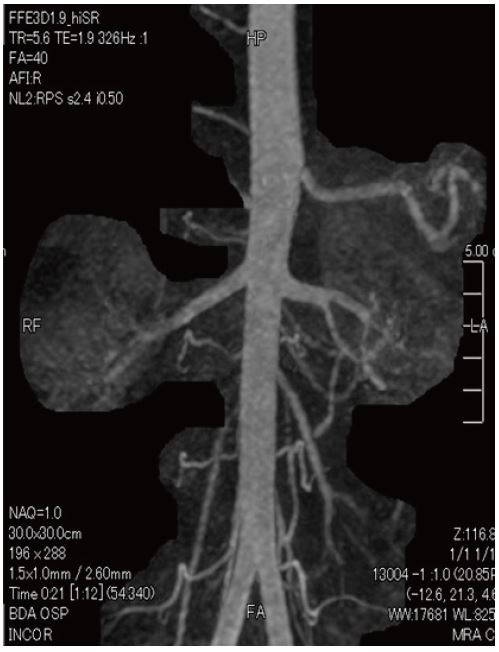

Ангіо-МРТ з використанням методу Time-SLIP

46-річна людина, гіпертонік, ангіо-МРТ з використанням методу Time-SLIP

Метод Time-SLIP

Техніка з використанням парамагнитного контрасту